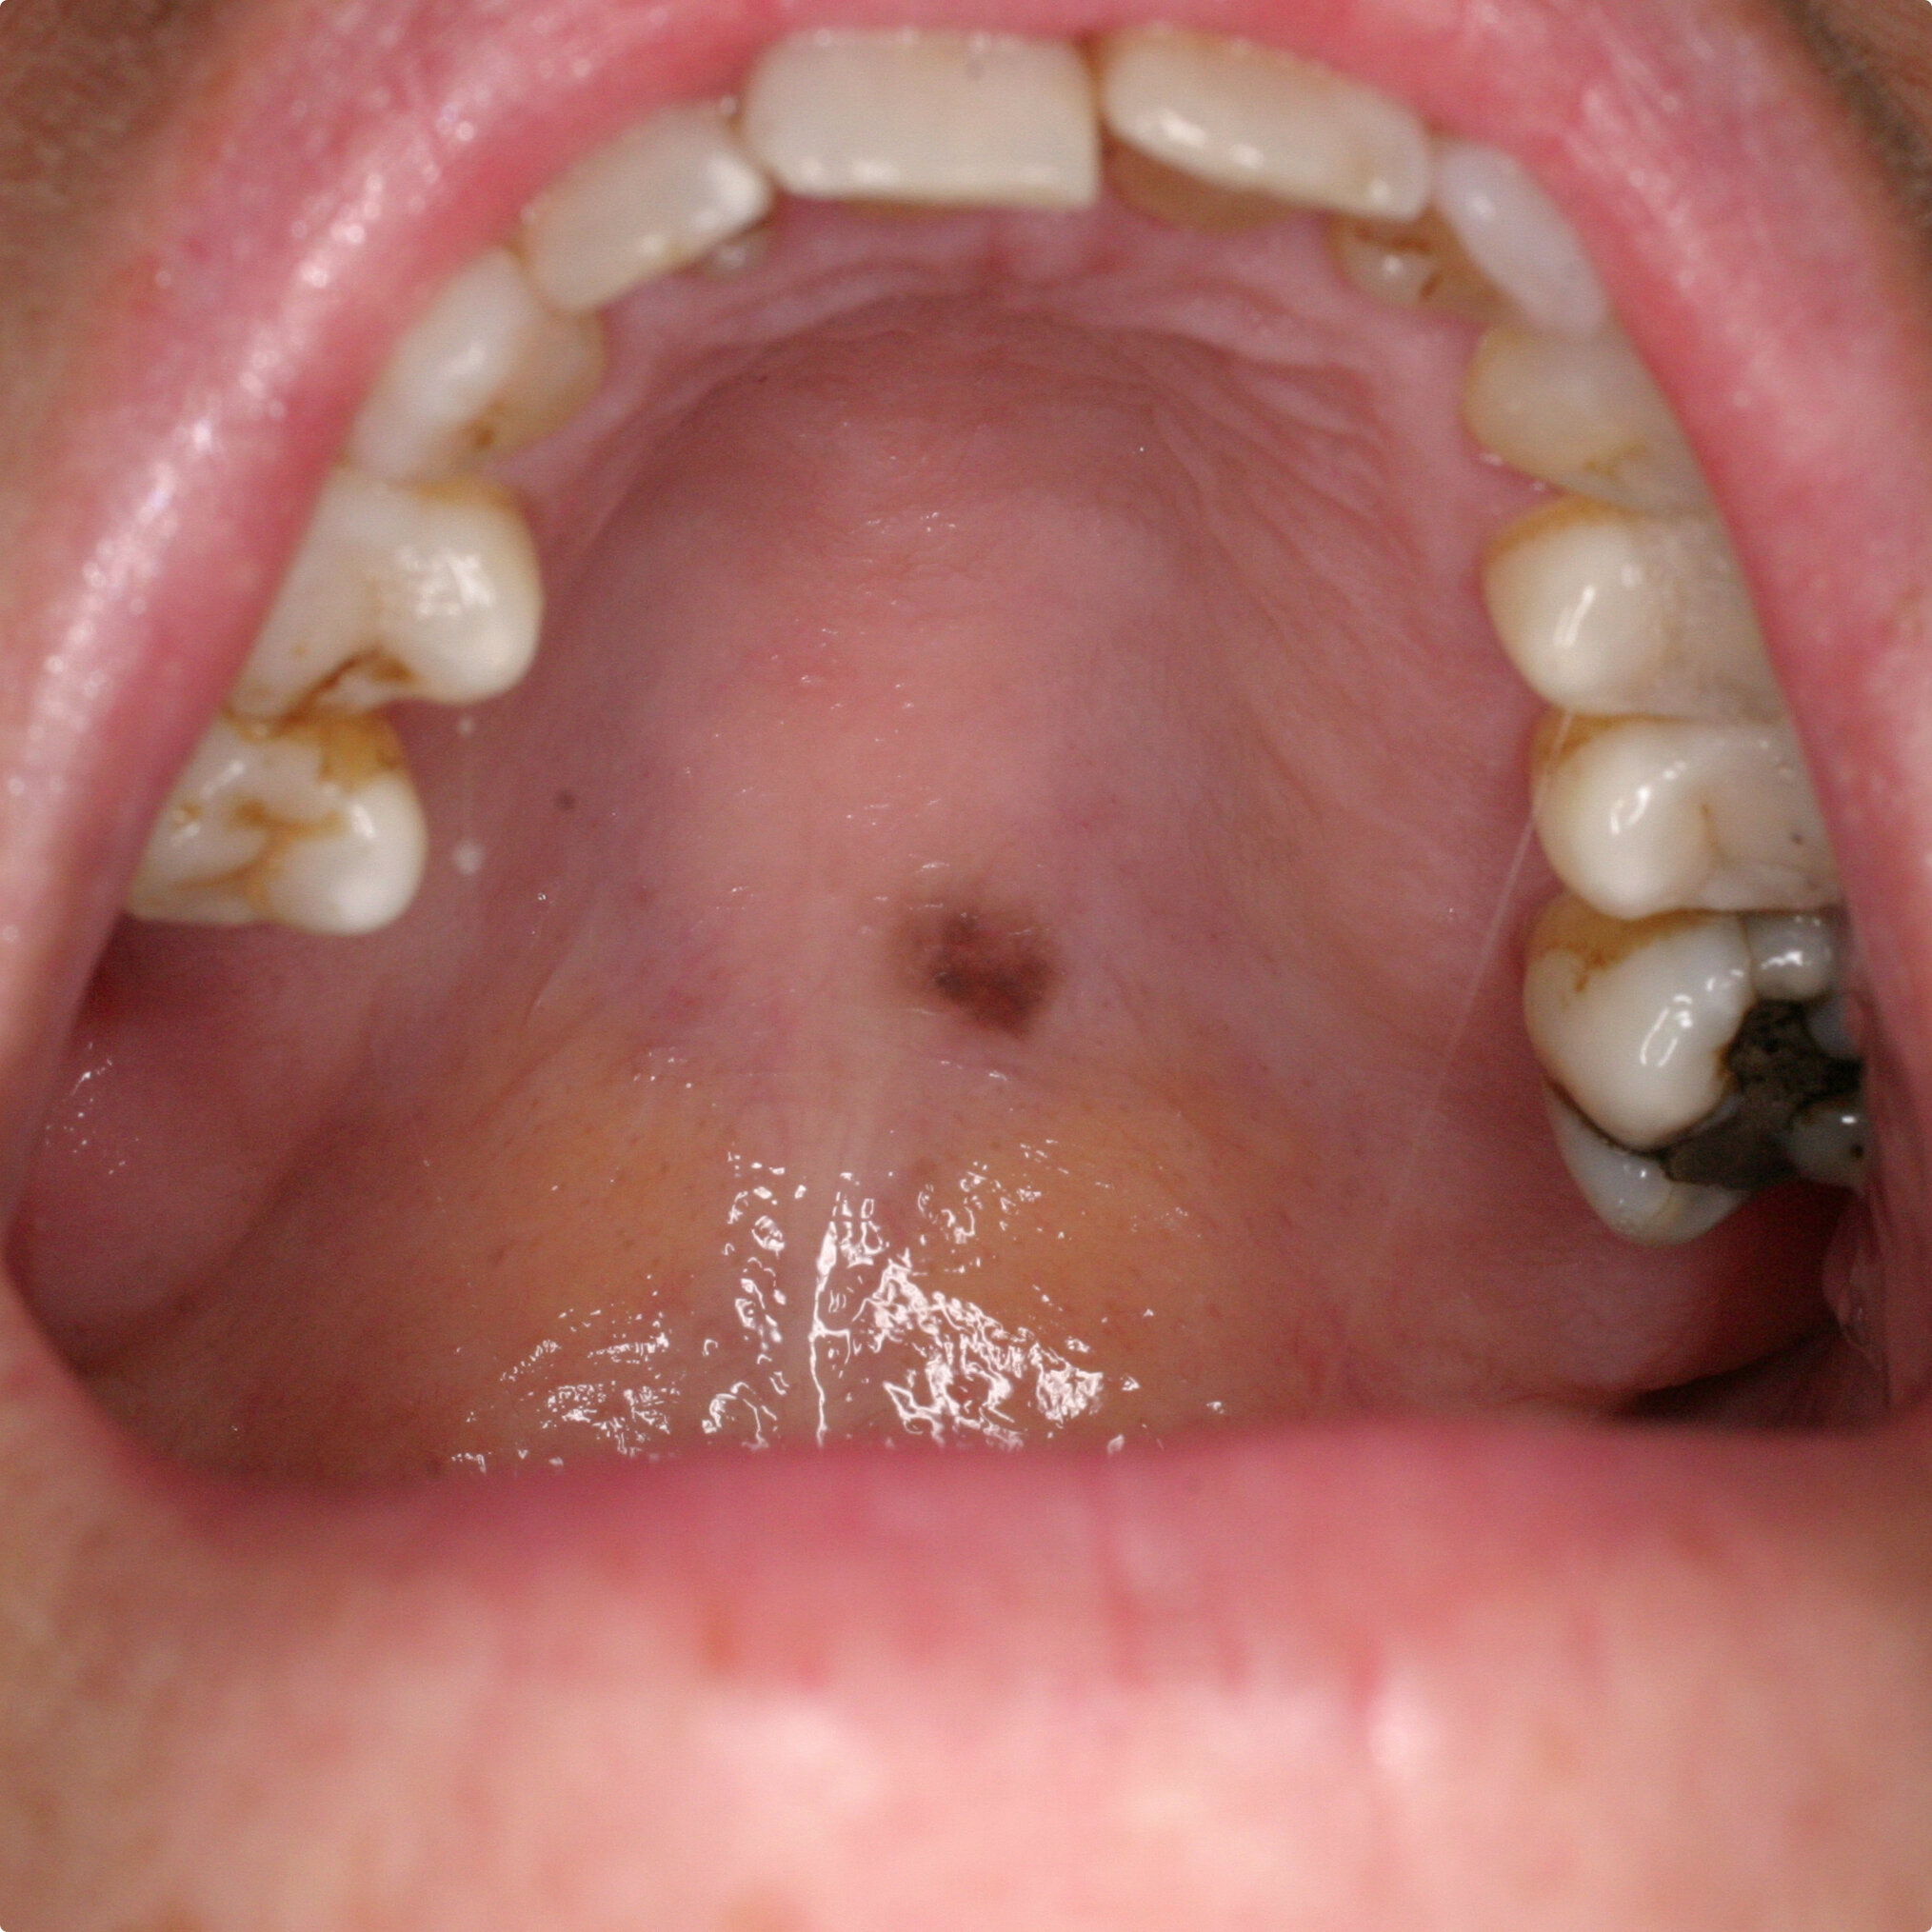

Confused by health insurance options? Discover the key difference between PPO and HMO plans to make an informed choice. Our guide breaks down provider networks, out-of-pocket costs, and referral requirements, helping you compare plan types and premiums to find the best managed care coverage for your medical needs and budget.